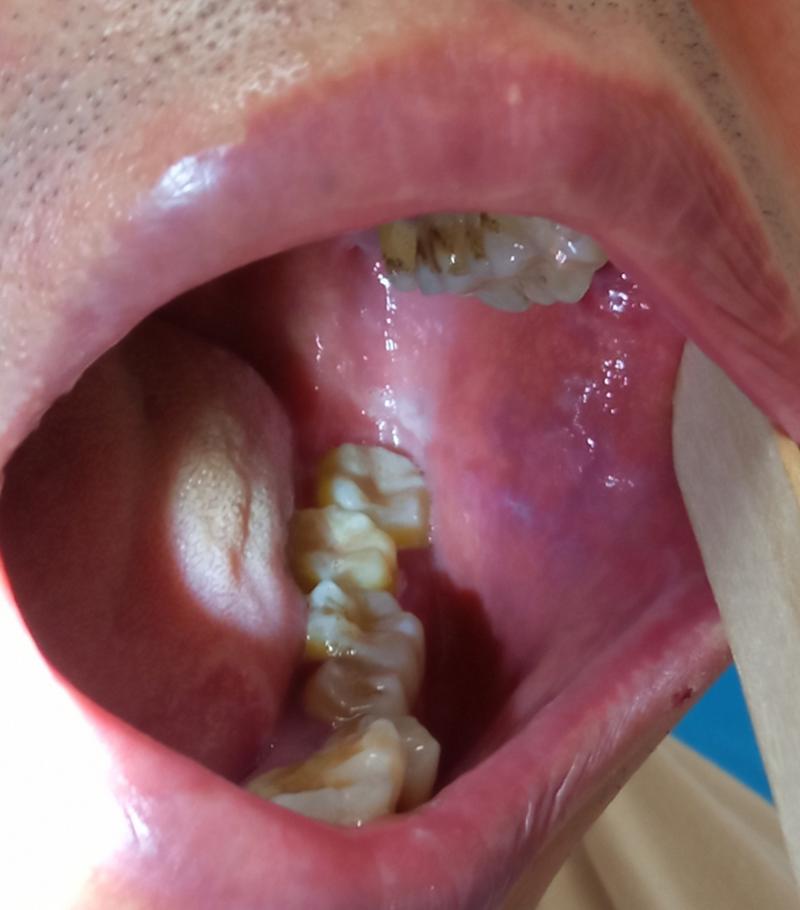

第二大元凶:可能是“发炎”的信号——扁桃体结石

如果你的黄颗粒主要出现在喉咙两侧,那就要考虑是不是扁桃体结石了。

它是什么? 扁桃体表面有许多凹陷的“隐窝”,当食物残渣、脱落的细胞和细菌在这些隐窝内堆积、钙化后,就会形成黄白色或黄褐色的、质地坚硬的颗粒状物,这就是扁桃体结石。

典型症状:

- 感觉喉咙有异物感,咳不出来咽不下去。

- 持续的口臭,是扁桃体结石最典型的伴随症状。

- 有时会引起反复的咽喉疼痛或扁桃体发炎。

如何判断? 对着镜子张开嘴,压住舌头,用光照射喉咙两侧,有时能肉眼看到白色或黄色的“小石子”。